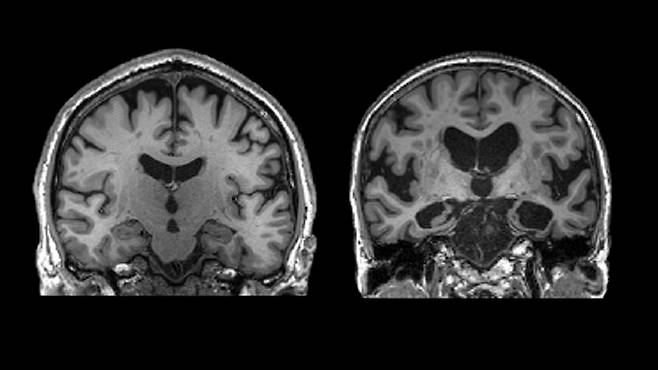

중년에 접어들면 대뇌 백질과 해마의 퇴화가 시작된다. 백질은 우리 뇌의 네트워크를 이뤄 복잡한 작업을 수행하게 해주는 부위다. 해마는 기억, 감정, 학습을 담당하며 우리의 정체성을 이루는 핵심 부위다.

여성은 중년에 폐경이라는 급격한 전환기를 맞이한다. 폐경은 일반적으로 40대 후반에 시작되는데, 해마 부피가 줄고 백질의 부담이 커진다.

유산소 운동의 중요성을 빼놓을 수 없다. 유산소 운동은 중년부터 쪼그라드는 해마나 백질의 부피를 유지하고 기능을 개선하는 데 큰 도움을 준다.

이들은 마치 치매의 침투를 막는 방어막을 뇌에 두른 듯하다. 뇌 기능 퇴화를 겪지 않을 뿐만 아니라 신체 기능도 더 뛰어나다.

슈퍼에이저와 별개로 뇌에 병리가 쌓여도 또렷한 정신 상태를 유지하는 사람도 있다. 뇌 영상을 찍으면 분명 치매에 접어들어야 하는데 증상이 안 나타난다. 이들 역시 치매에 강한 저항력을 가진 것처럼 보인다.

병리학자들은 이를 ‘인지 예비능(cognitive reserve)’이라는 개념으로 설명한다. 뇌에 나타나는 병적 변화를 더 잘 견디고 기능을 유지하게 해주는 뇌의 ‘예비적인 능력’을 일컫는 말이다. 마치 뇌가 보조 배터리를 지닌 것과 비슷하다.